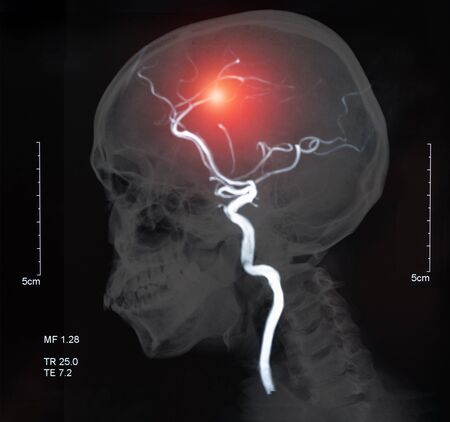

뇌졸중은 뇌 일부에 혈액을 조달하는 혈관이 막히거나 파열돼 뇌 손상을 발생시키는 질환으로 의식장애, 부분마비, 언어장애 등 각가지 신경학적 결함을 대동한다고 하고요. 뇌졸중은 뇌혈관 질환과 같은 말이며 우리나라에서는 중풍이라고 곧잘 말하고 있죠.

뇌졸중은 주로 동맥경화증으로 뇌조직으로의 혈액 공급이 차단돼 뇌 손상을 촉발하고 흡연, 과음, 운동 부족, 비만 등이 원인이고요.뇌졸중은 보통과 다르게 추운 날씨에 생성되기 쉽다고 하는데요. 추울 때는 혈관이 수축하고, 더울 때는 팽창하기에 추운 곳에서 급격히 실내로 들어오면 혈관이 급작스레 확대되기 때문이예요.

뇌졸중 징후이 발생하면 MRI로 진단해 뇌졸중 예방과 선제적 치료를 하더라고요. 뇌졸중 진단을 받으면 증상의 정도와 환자의 정황에 따라 약물치료와 수술이 이뤄진다고 하더라고요. 근래에는 시술이 발달해 골든타임 내에 병원에 오면 막힌 혈관에 스텐트라는 그물을 투여해 혈전을 삭제하는 뇌혈관 중재를 통해 후유증을 감소시키며 실리적으로 치료할 수 있고요.